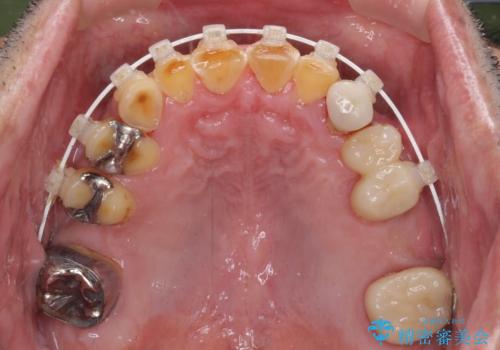

奥歯の欠損が散見されており、銀歯の装着されている歯も多いため、ワイヤー矯正にて歯列を調整し、その後オールセラミッククラウンにて補綴治療を行うこととしました。

反対咬合改善には奥歯の咬み合わせをしっかりと改善させることが必要となりますが、奥歯に欠損が多いため、矯正治療が難航することが予想されます。

矯正治療は想定通り長期化しましたが、しっかりと奥歯の咬み合わせを向上させて前歯の被蓋を改善させることができました。